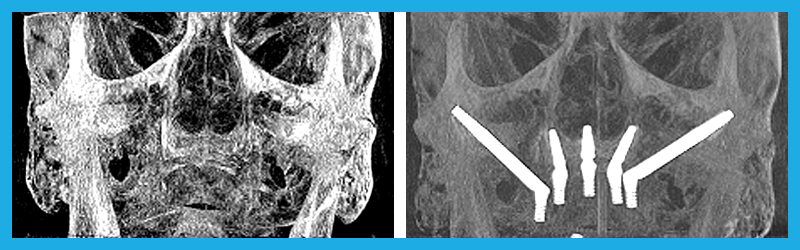

Before and After

Zygomatic Implants